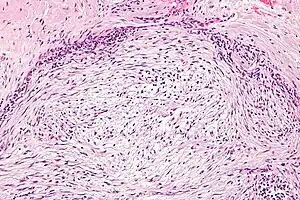

The microscopic histopathology of hematoxylin and eosin stained nodular fasciitis tumors (see above and three below figures) consists of spindle-shaped myofibroblastic cells (i.e. cells with features of smooth muscle cells and fibroblasts.).[9] These cells are in a myxoid (i.e. more blue or purple compared to normal connective tissue because of excessive uptake of the hematoxylin stain) or a collagenous (high content of collagen fibers) tissue background. The neoplastic myofibroblasts are arranged in whorls and/or short bundles. These cells may show high rates of replicating as judged by their mitotic index but these mitoses are normal in appearance. The tumor tissues often contain red blood cells, lymphocytes and giant osteoclast-like giant cells and may contain sites of bone-like tissue.[11] NF is sometimes classified into three subtypes based on its predominant histopathological pattern: myxoid or reactive (type I), cellular (type II), and fibrous (type III).[5] These patterns appear related to the duration of the lesion with the myxoid variant tending to have the shortest duration and the cellular and fibrous variants tending to have progressively longer durations.[15]Immunohistochemical analyses indicate that the cells in NF usually express smooth muscle actin, muscle specific actin, and vimentin proteins but generally do not express CD34, S-100 protein, desmin, trypsin, factor VIII, F4/80 (also termed macrophage-specific antigen), or HLA-DR1 proteins.[11] Uncommonly, the cells in NF tumors also express the CD68 (a histiocyte-specific marker) protein.[5]

Intermediate magnification